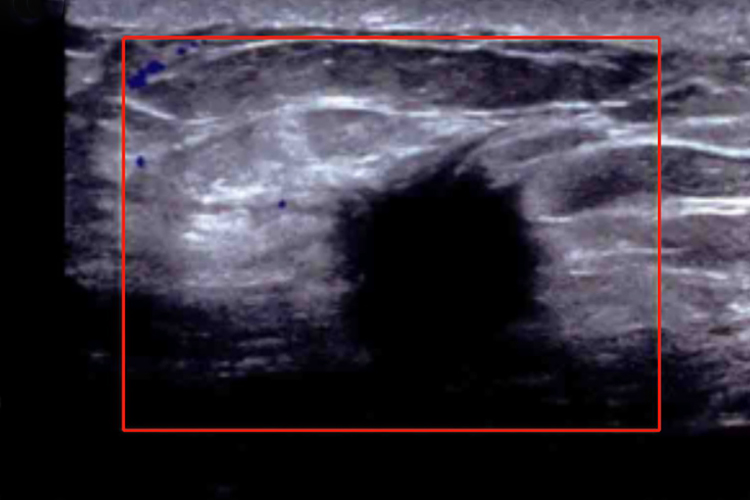

恶性结节

主要表现为异常回声的不规则形肿物,边界模糊,肿物与周围组织之间没有明显的界线,或者在肿物的边缘伸出锐利的细线,呈毛刺状。